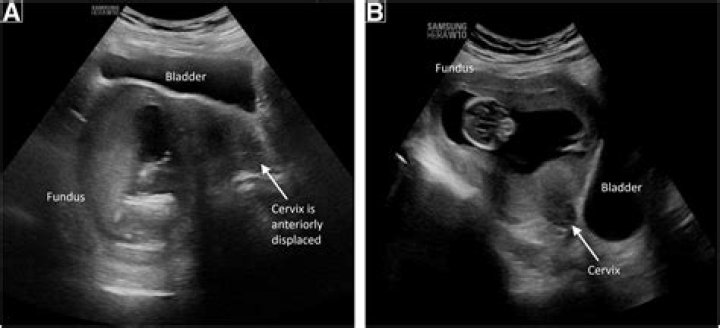

Having a tilted uterus (also called an inverted uterus, tilted cervix, or retroverted uterus) is perfectly normal. It just means that your uterus is tilted backward toward your spine rather than forward. A retroverted uterus has no effect on your ability to get pregnant.

Retroversion of the uterus is common. Approximately 1 in 5 women has this condition. The problem may also occur due to weakening of the pelvic ligaments at the time of menopause. Scar tissue or adhesions in the pelvis can also hold the uterus in a retroverted position.

The positioning of the uterus can change from anteversion to retroversion due to the filling of bladder or during pregnancy; however, changing from retroverted to anteverted position without prior pregnancy or endometriosis is rather uncommon.